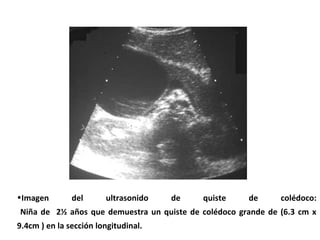

•Imagen del ultrasonido de quiste de colédoco:

Niña de 2½ años que demuestra un quiste de colédoco grande de (6.3 cm x

9.4cm ) en la sección longitudinal.